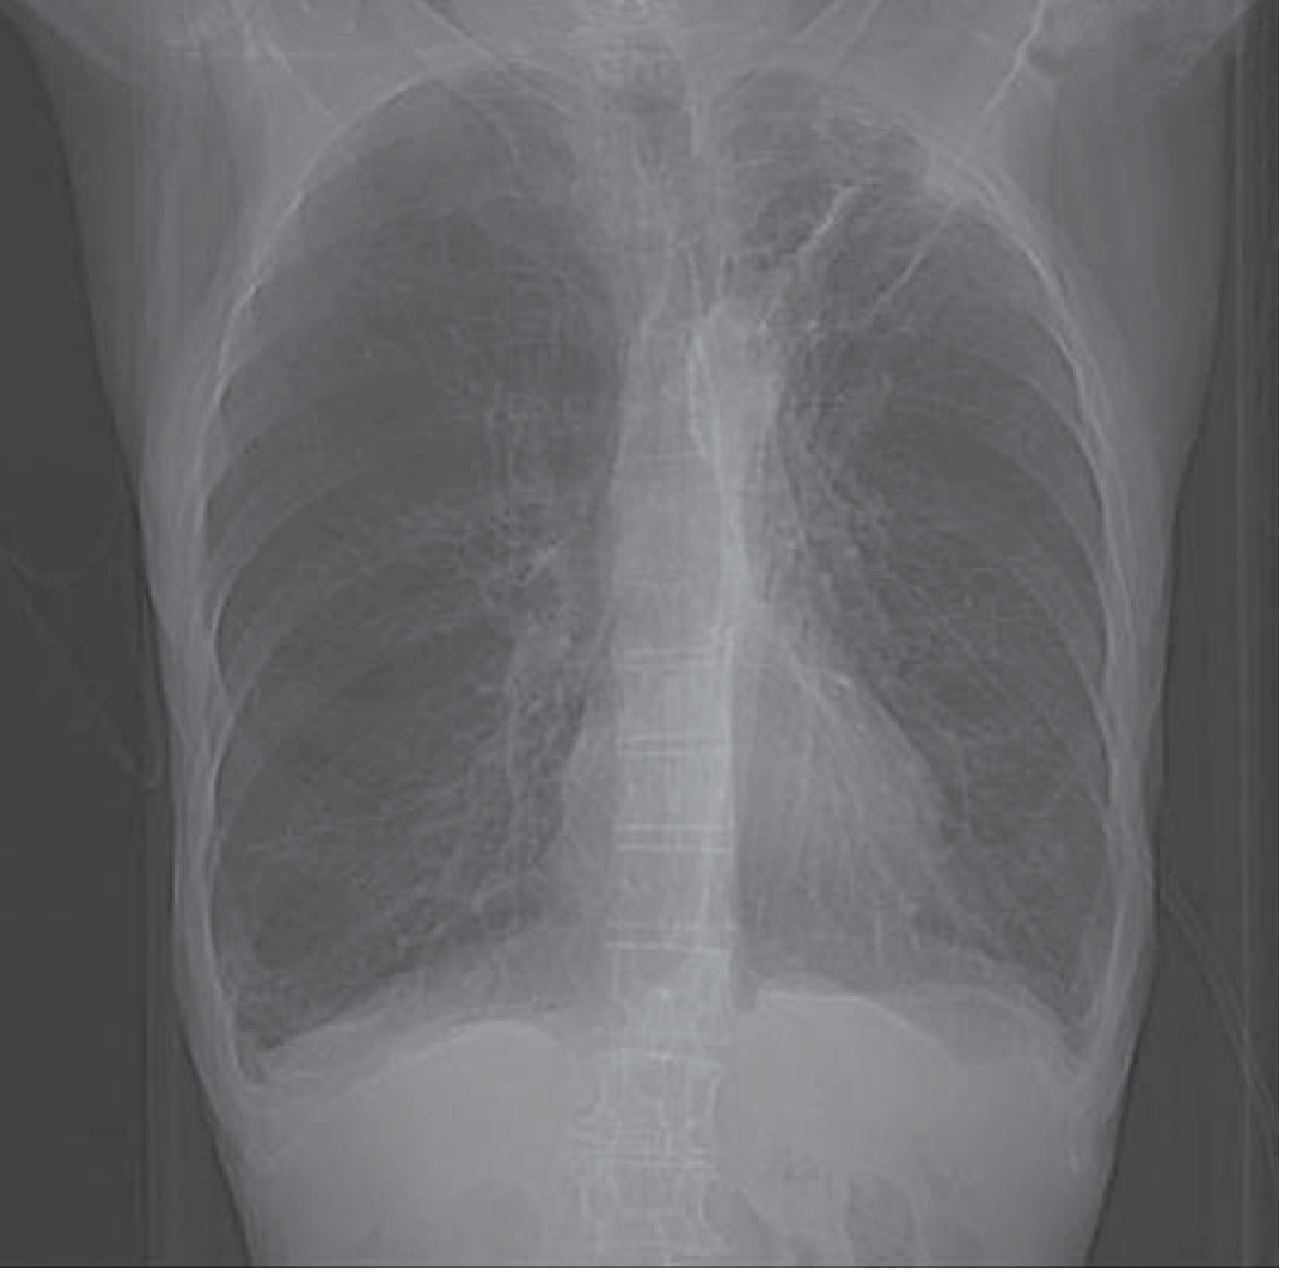

Chest X-ray in COPD

Posteroanterior chest radiograph in a patient with COPD — Tintinalli's Emergency Medicine

A plain chest radiograph is useful in demonstrating changes suggestive of COPD (hyperinflation, bullous changes). CT of the chest may reveal emphysema or an interstitial process not suggested by plain radiographs. — Fishman's Pulmonary Diseases and Disorders, p. 439